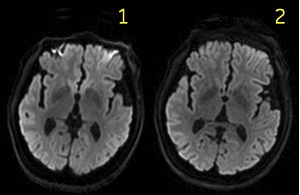

| 1 | Original uncorrected images. |

| 2 | Images that have Distortion Correction applied. |